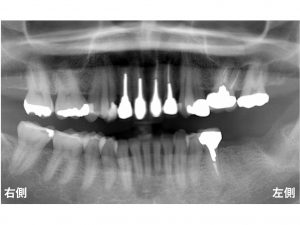

以下は、初診時です。

下顎の左側の奥歯が2歯欠損している方です。

以下は、インプラント手術直後です。

使用したインプラントは、

ストローマンインプラントです。

治療期間は、

インプラントを埋入後に約2〜3ヶ月程度お待ちいただきます。

その後、型を取り、

約2週間後にオールセラミックの被せ物を装着して終了です。